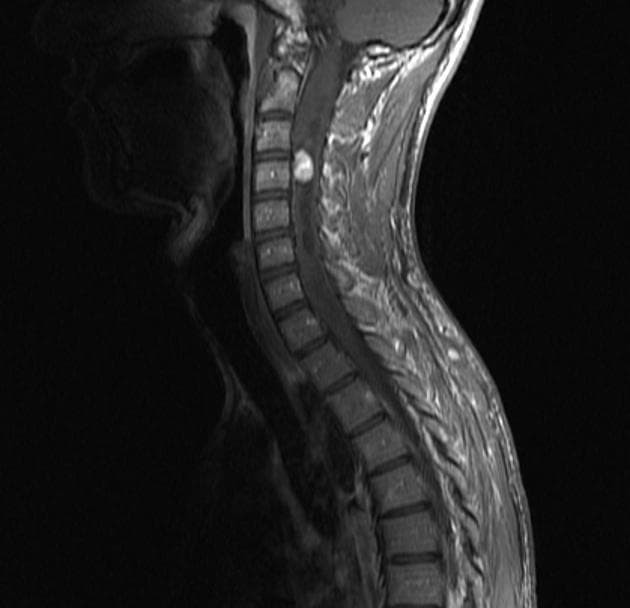

Von Hippel-Lindau Disease with Spinal Hemangioblastoma (Bệnh Von Hippel-Lindau với u mạch bào ở tủy sống)